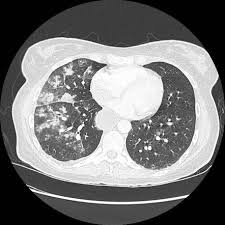

Also known as Mendelsons syndrome pulmonary acid aspiration syndrome is a dangerous condition in which acid and other stomach contents may enter the airway and ultimately the lungs. Acid aspiration causes alveolar and interstitial inflammation with edema and leukocyte infiltration. If the aspirated material is infected it is likely to cause pneumonia and lung abscess but if sterile and highly acid the consequences are liable to be even more dire.

Effects Of Pulmonary Acid Aspiration On The Lungs And Extra Pulmonary Organs A Randomized Study In Pigs Critical Care Full Text